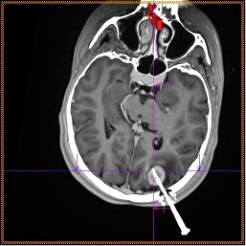

Рис. 13г. Стереотаксическая биопсия опухоли головного мозга под ПДКТ-контролем (этап контроля положения биопсийной иглы в опухоли с использованием объединенных (совмещенных) данных: ПДКТ для визуализации иглы и МРТ для визуализации опухоли)